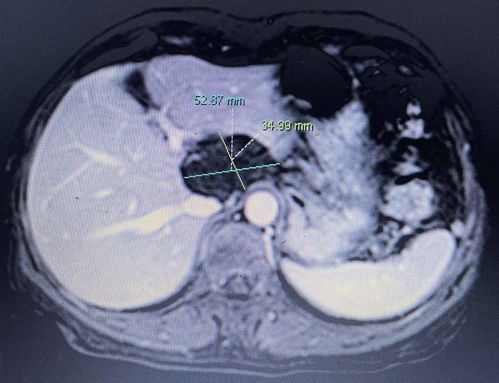

故事从一次不幸的体检开始。这位年轻的患者,面对人生中最严峻的挑战肝癌晚期。当体内的肿瘤长大到十多公分,且已经出现转移的迹象时,生命的钟声开始敲响警钟。面对这样的噩耗,他并未沉溺于绝望之中。